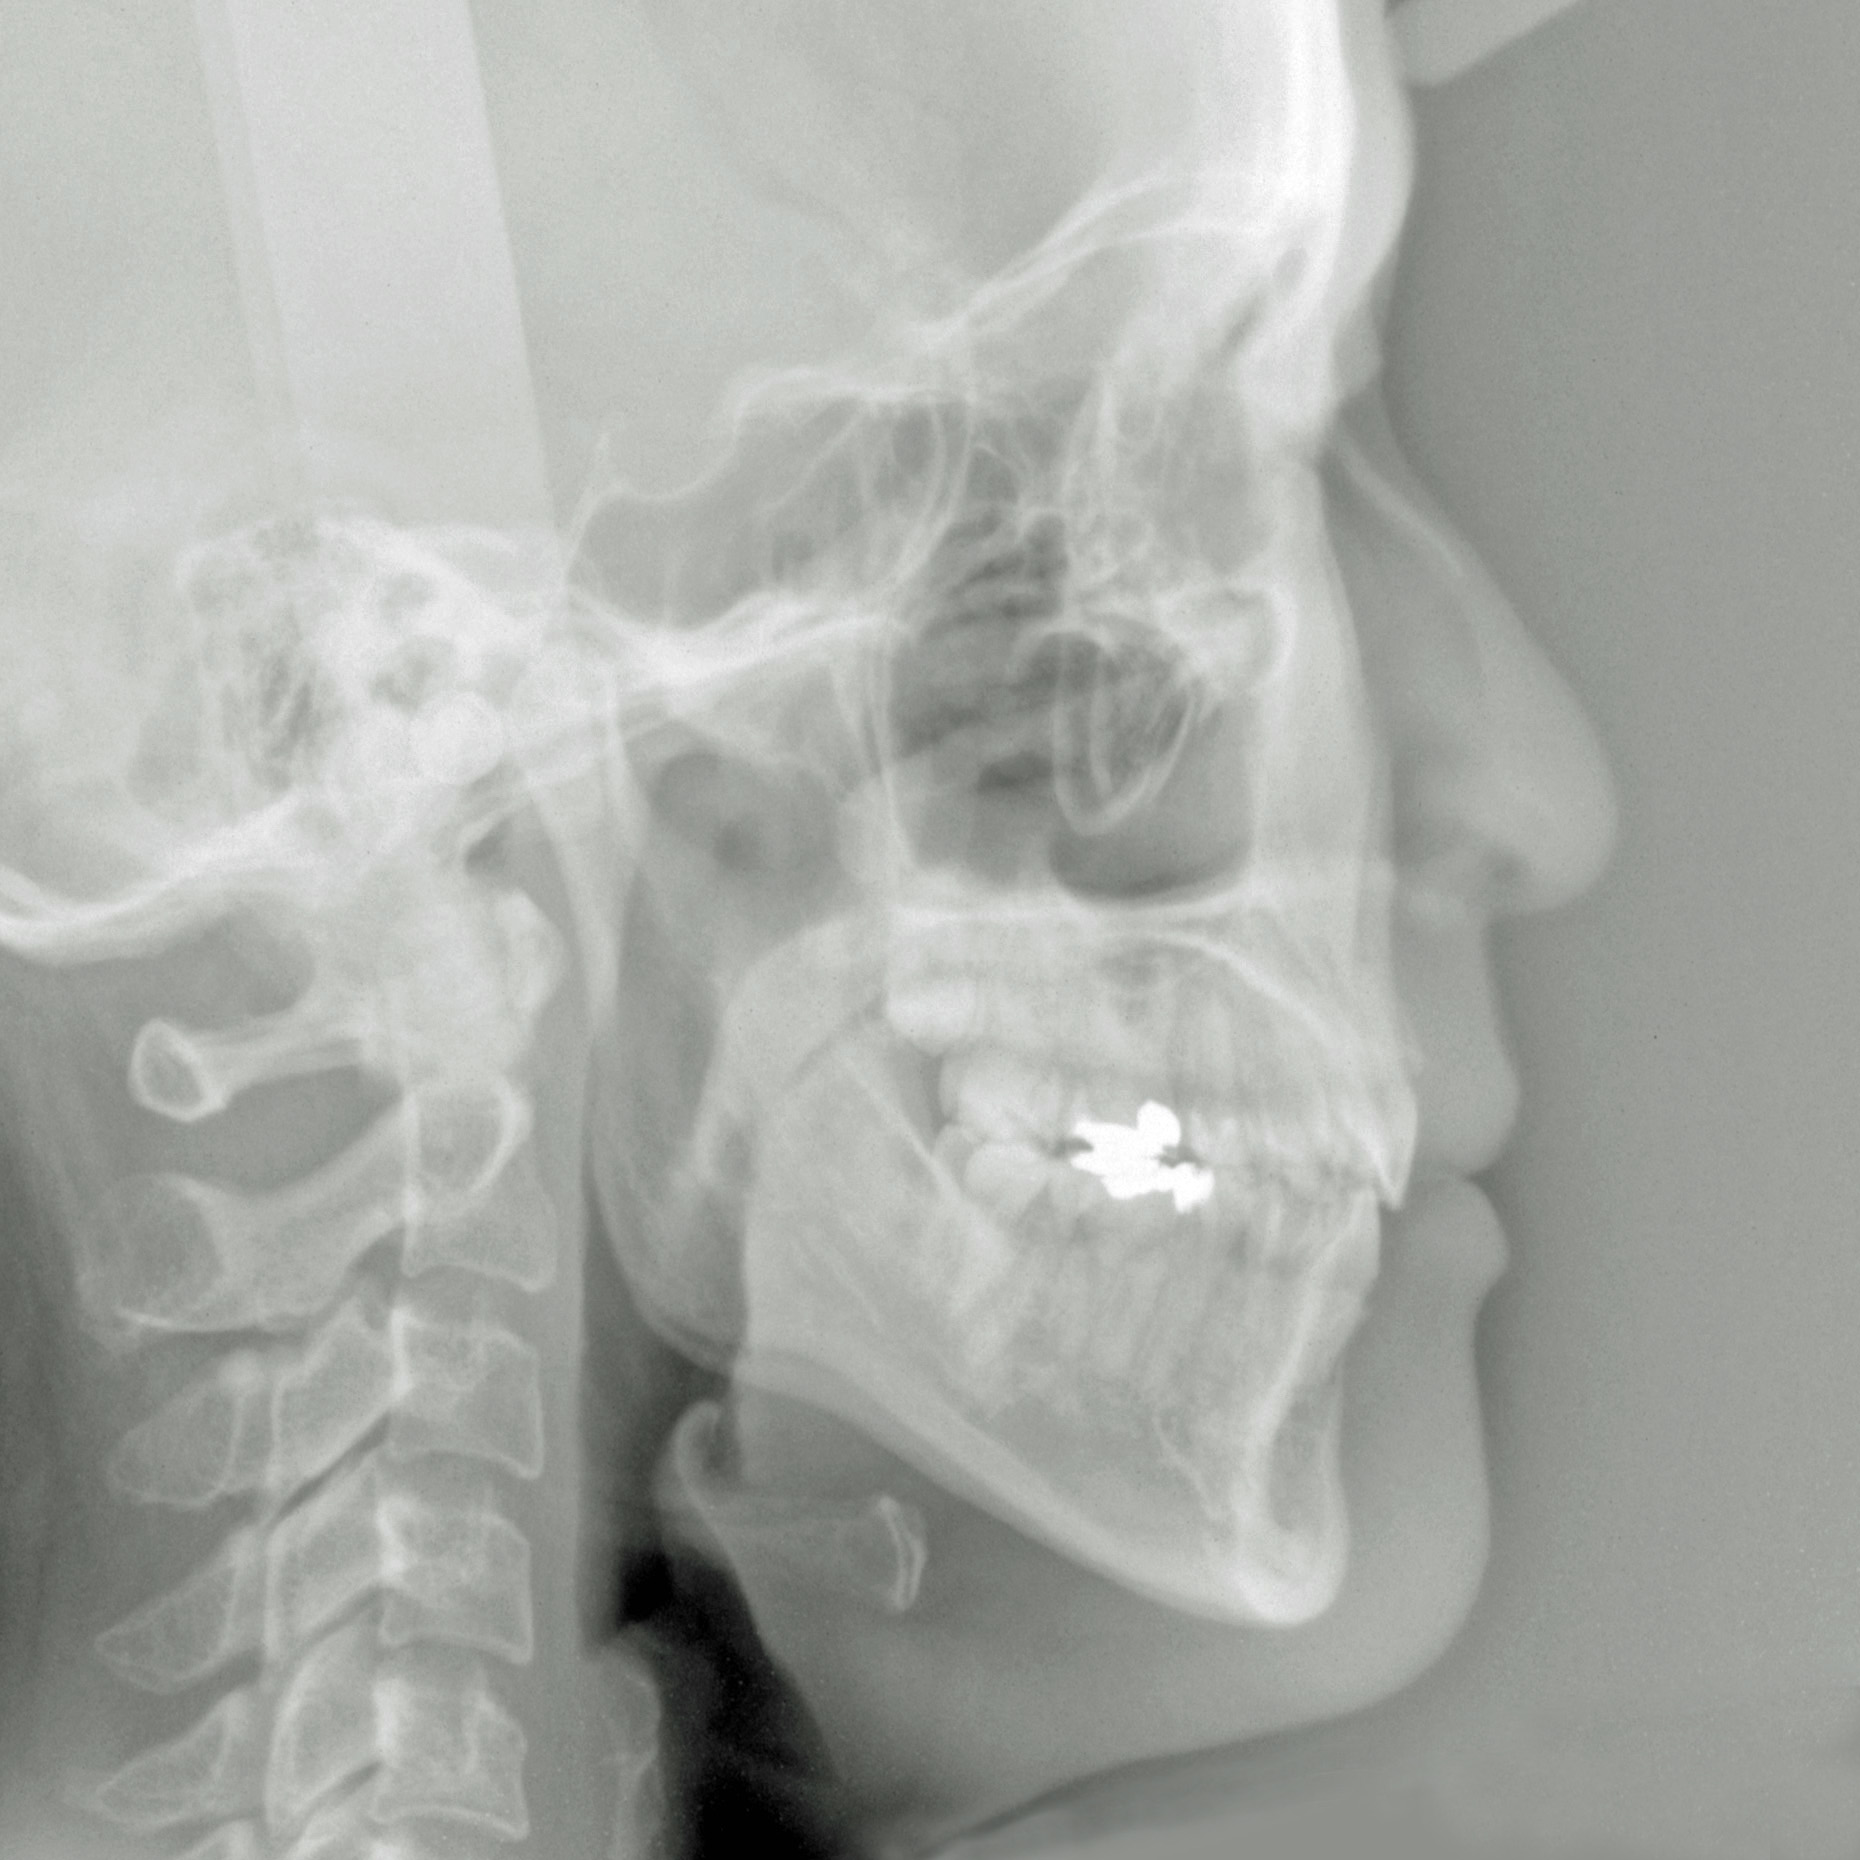

新着情報 516治療後セファロ側面 Tweet 投稿日 : 2020年03月27日(金)カテゴリー : コメントを残す コメントをキャンセルメールアドレスが公開されることはありません。 * が付いている欄は必須項目ですコメント 名前 * メール * サイト 43歳 女性「 口もとを 下げたい」( 上下顎前突症 ) ≫